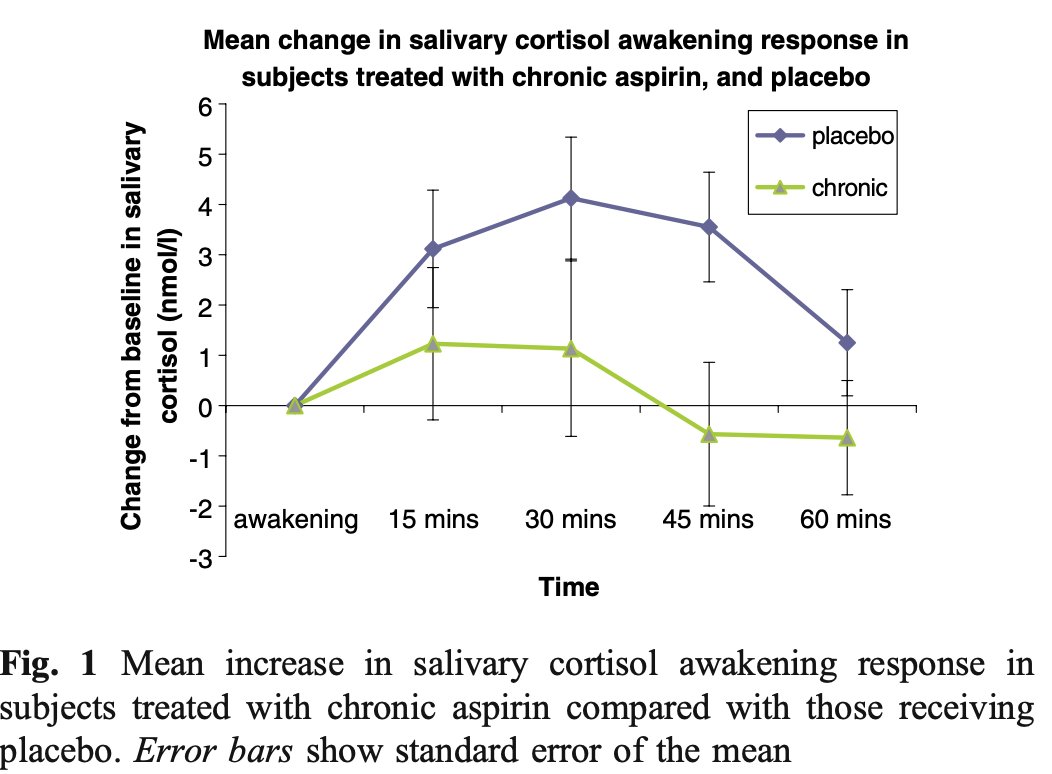

In fact, aspirin has consistently and unequivocally shown to reduce both the incidence AND the mortality of various cancers.

ASPIRIN is the lifespan extending intervention that everyone has been searching for.

It has consistently been shown to reduce the risk of dying from any cause, demonstrating its broad ranging protective effects.

It has consistently been shown to reduce the risk of dying from any cause, demonstrating its broad ranging protective effects.